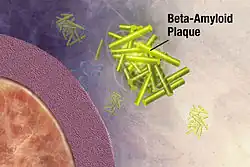

Alzheimer's disease

Alzheimer's disease is an incurable neurodegenerative disease which most often affects the elderly and accounts for more than half of all cases of dementia. Its exact cause remains unknown, but the disease is identified as a protein misfolding disease. Alzheimer's is associated with toxic aggregations of the amyloid beta (Aβ) peptide, caused by Aβ misfolding and clumping together with other Aβ peptides. These Aβ aggregates then grow into significantly larger senile plaques, a pathological marker of Alzheimer's disease.[49][50][51] Due to the heterogeneous nature of these aggregates, experimental methods such as X-ray crystallography and nuclear magnetic resonance (NMR) have had difficulty characterizing their structures. Moreover, atomic simulations of Aβ aggregation are highly demanding computationally due to their size and complexity.[52][53]

Preventing Aβ aggregation is a promising method to developing therapeutic drugs for Alzheimer's disease, according to Naeem and Fazili in a literature review article.[54] In 2008, Folding@home simulated the dynamics of Aβ aggregation in atomic detail over timescales of the order of tens of seconds. Prior studies were only able to simulate about 10 microseconds. Folding@home was able to simulate Aβ folding for six orders of magnitude longer than formerly possible. Researchers used the results of this study to identify a beta hairpin that was a major source of molecular interactions within the structure.[55] The study helped prepare the Pande lab for future aggregation studies and for further research to find a small peptide which may stabilize the aggregation process.[52]

In December 2008, Folding@home found several small drug candidates which appear to inhibit the toxicity of Aβ aggregates.[56] In 2010, in close cooperation with the Center for Protein Folding Machinery, these drug leads began to be tested on biological tissue.[35] In 2011, Folding@home completed simulations of several mutations of Aβ that appear to stabilize the aggregate formation, which could aid in the development of therapeutic drug therapies for the disease and greatly assist with experimental nuclear magnetic resonance spectroscopy studies of Aβ oligomers.[53][57] Later that year, Folding@home began simulations of various Aβ fragments to determine how various natural enzymes affect the structure and folding of Aβ.[58][59]